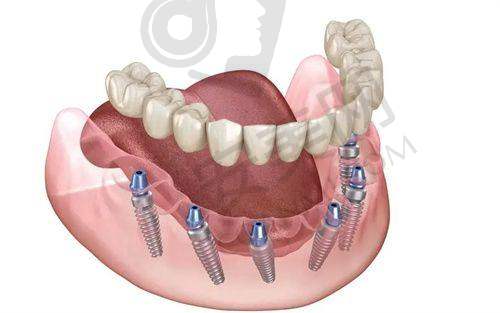

根据我的检查结果,医生为我制定了个性化的种植牙方案。他向我介绍了不同品牌和型号的种植体,并详细说明了它们的优缺点和适用情况。就像重庆女子乘“黄色法拉利”去内蒙古有自己独特的选择一样,医生也根据我的需求和经济状况,为我推荐了更适合我的种植体。在制定方案的过程中,医生充分尊重我的意见,耐心解答我的每一个疑问。更终,我们确定了种植牙的具体方案,包括种植体的品牌、种植的位置和数量等。

经过一段时间的修复,种植牙完全融入了我的口腔。现在,我可以像正常牙齿一样咀嚼食物,再也不用担心牙齿缺失的问题了。种植牙的外观和真牙非常相似,几乎看不出是人工种植的。而且,它的稳定性也良好,不会像传统假牙那样容易松动。自从种了牙,我的生活质量有了较大的提高,我又可以尽情享受各种美食了。朋友们都说我看起来年轻了好几岁,这让我更加自信。

太原达美联合口腔医院的种植牙技术有特别多特色。首先,医院采用的是精良的数字化种植技术。通过口腔 CT 扫描和计算机模拟,医生可以严谨地规划种植体的位置和角度,大大提高了手术的成功几率。其次,医院的种植体品牌丰富,患者可以根据自己的需求和经济状况进行选择。再者,医院的医生团队会为每一位患者制定个性化的治疗方案,充分考虑患者的口腔状况和个人需求。末尾,医院提供完善的术后跟踪服务,医生会定期回访患者,了解修复情况并给予指导。